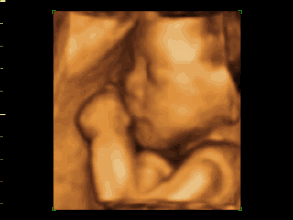

▲图片来源于网络